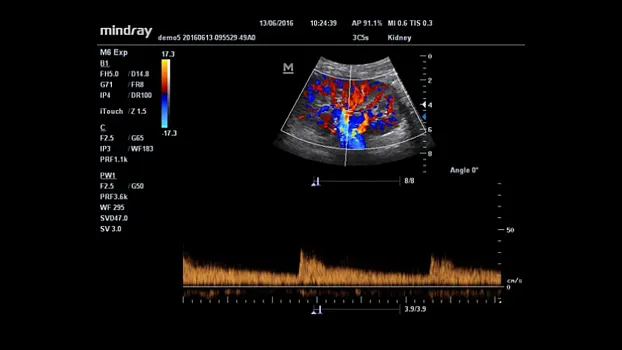

Клинические изображения

3С5s |

Конвексный датчик для абдоминальных исследований, акушерства, гинекологии, урологии и сосудистых исследований |